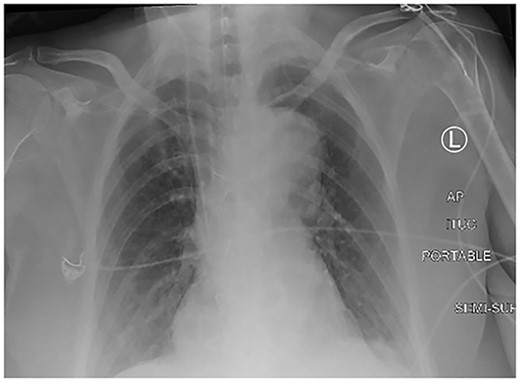

A 61-year-old female with known Marfan Syndrome was admitted to the emergency department with 3-day history of abdominal pain, nausea, vomiting and bowels not opening. Past medical history included three previous episodes of Type A aortic dissection, recent aortic root and ascending aorta replacement alongside bioprosthetic aortic valve replacement. She was an ex-smoker and usually independent at home. On presentation, the patient was haemodynamically stable and apyrexial. Biochemical results were unremarkable except for a Lactate dehydrogenase (LDH) of 309 and a C-reactive protein (CRP) of 101. On examination, she had a diffusely tender and distended abdomen, without signs of peritonism. An erect chest X-ray shows left pleural effusion with a dilated aortic root (Fig. 1). A computed tomography (CT) of thorax, abdomen and pelvis was requested, which demonstrated a caecal volvulus with a dilated cecum of 8.8 cm and upstream small bowel dilatation with air fluid levels, and a chronic aortic dissection extending from the ascending thoracic aorta to the common iliac (Figs 2–4). Following consultation between radiologists, cardiothoracic surgeons and general surgeons, she underwent an emergency laparotomy and right hemicolectomy with side-to-side ileocolic anastomosis. Intraoperatively, the caecal volvulus, comprising a dilated ascending colon measuring up to 10 cm, was delivered and resected along with its mesentery. The patient was admitted to the intensive care unit post-operatively for close blood pressure monitoring and control and stepped down to level 3 wards on day-2 post-operation. Her operation was complicated by a small infected wound haematoma thatwas managed with a 5-day course of ciprofloxacin. A CT of the abdomen and pelvis to investigate a rising CRP on day-9 revealed a subcapsular liver haematoma thath was managed conservatively. The patient was discharged 12-days post-operatively. Histology from the resected colon showed evidence of ischaemia in keeping with a closed loop obstruction such as caecal volvulus. There was also an incidental T1 N0 colonic tumour arising from a sessile serrated polyp and two other serrated polyps. A colonoscopy to inspect the remaining colon has been arranged.

Erect chest X-ray demonstrating left pleural effusion and an unfolded, dilated aortic arch.